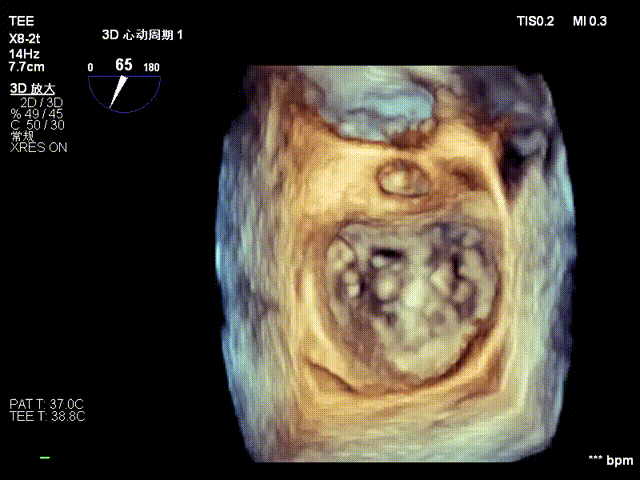

术中操作(关键步骤超声)

在全麻下,于心尖入路完成ValveClamp®装置植入。术中多学科团队密切配合,超声全程实时指导操作。最终,于2偏3区成功植入一枚Ⅲf夹子,一次夹合完成。前叶夹合量12mm,后叶夹合量10mm,反流降至1+,导管操作时间30分钟。术后平均跨瓣压差3mmHg。

术中剪影